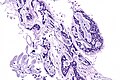

Adenoid cystic carcinoma. H&E stain. | |

| LM | cribriform architecture (other patterns: solid, cords, (bilayered) tubules), cystic spaces filled with basophilic material, scant cytoplasm in most cells, nucleus - small, hyaline stroma |

- Cribriform architecture or pseudoglandular spaces (classic pattern) - important feature.

- Other patterns: solid, cords, (bilayered) tubules.

- Cystic spaces filled with basophilic material (that is PAS +ve) - key feature.

- Scant cytoplasm in most cells (myoepithelial cells) - clear/eosinophilic.

- Moderate eosinophilic cytoplasm in the (rare) ductal cells.

- Nucleus - small.

- May be angulated (carrot-shaped) - myoepithelial cells; round/ovoid in ductal cells.

- Hyaline stroma.

The sections show a tumour with a cribriform architecture. The cystic spaces have basophilic material. The tumour cells are carrot-like and have scant/modest cytoplasm.